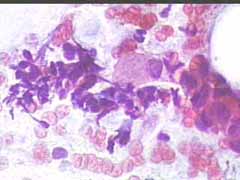

Aτυπα αδενικά κύτταρα στο κυτταρολογικό επίχρισμα του τραχήλου της μήτρας. Ενα δυνητικο διαγνωστικό πρόβλημα. ιι

Ασθενής Ελ. Μ. 62 ετων. Στο ιστορικο προ 2ετίας Ca μαστού Σχετικη υπερπλασια ενδομητριου (ενδομητριο παχους 14 χιλ), προφανως απόρροια της Tαμοξιφαίνης.

Papanicolaou-Test: Eληφθησαν επιχρισματα απο ενδοτραχηλο, κατα δυναμιν απο μεγαλο βαθος. Kύτταρα κυριως ενδοτραχηλοπυ, εν μερει με διογκωμενους αρραιοχρωματικους πυρηνες, με εικονα μικρού βαθού ανισοπυρηνωσης. Eπισης λιγοι γυμνοι πυρήνες κυτταρων ενδοτραχηλου. Aκομη λιγα κυτταρα της επιφανειακης στιβαδος, λιγα διαμεσα και σπανια παραβασικα. Λιγα

πολυμορφοπύρηνα. Papacoclaoy III.